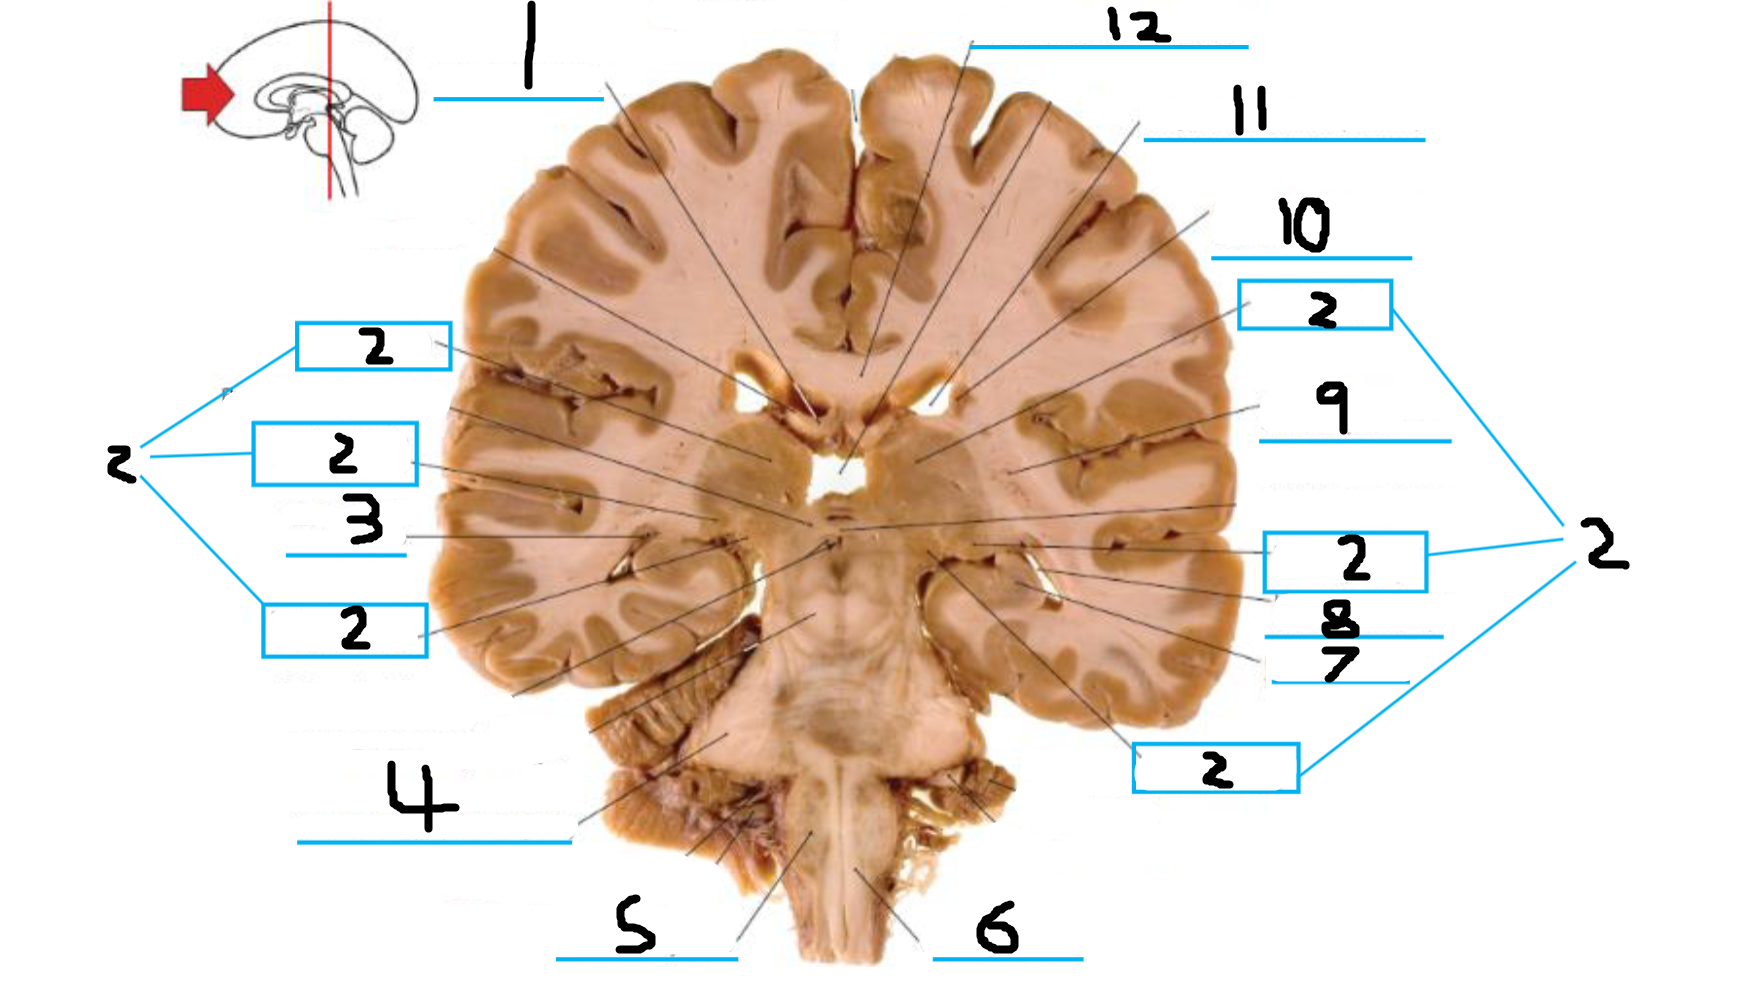

#1 is the:

Corpus Callosum

#2 is the:

Lateral Ventricle

#3 is the:

Septum Pellucidum

#4 is the:

#5 is the:

Insula

#6 is the:

Cingulate Gyrus

#7 is the:

Caudate

#8 is the:

Internal Capsule

#9 is the:

Putamen